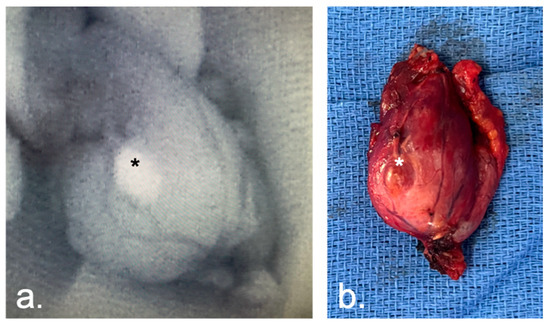

2.3. Imaging System